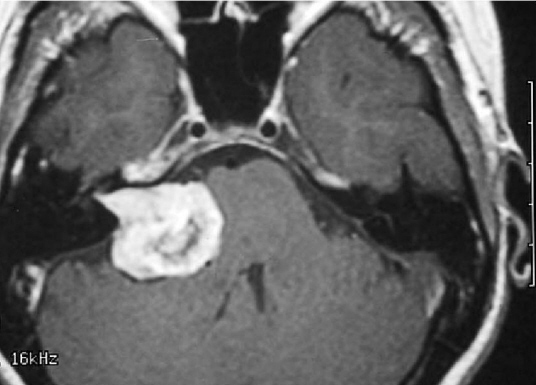

Upon my return to Los Angeles, I immediately wound up in the ER with hydrocephalus caused by a 3+ cm. acoustic neuroma compressing my brain stem by 50%. Two surgeries: one to implant a VP shunt and another to resect the tumor, left me in tip top shape – well…..except for the inconvenience of becoming totally deaf in one ear, and a few other minor annoyances such as inability to see straight, walk without listing to the right, close my eye, swallow — but I won’t bore you with that whole story.